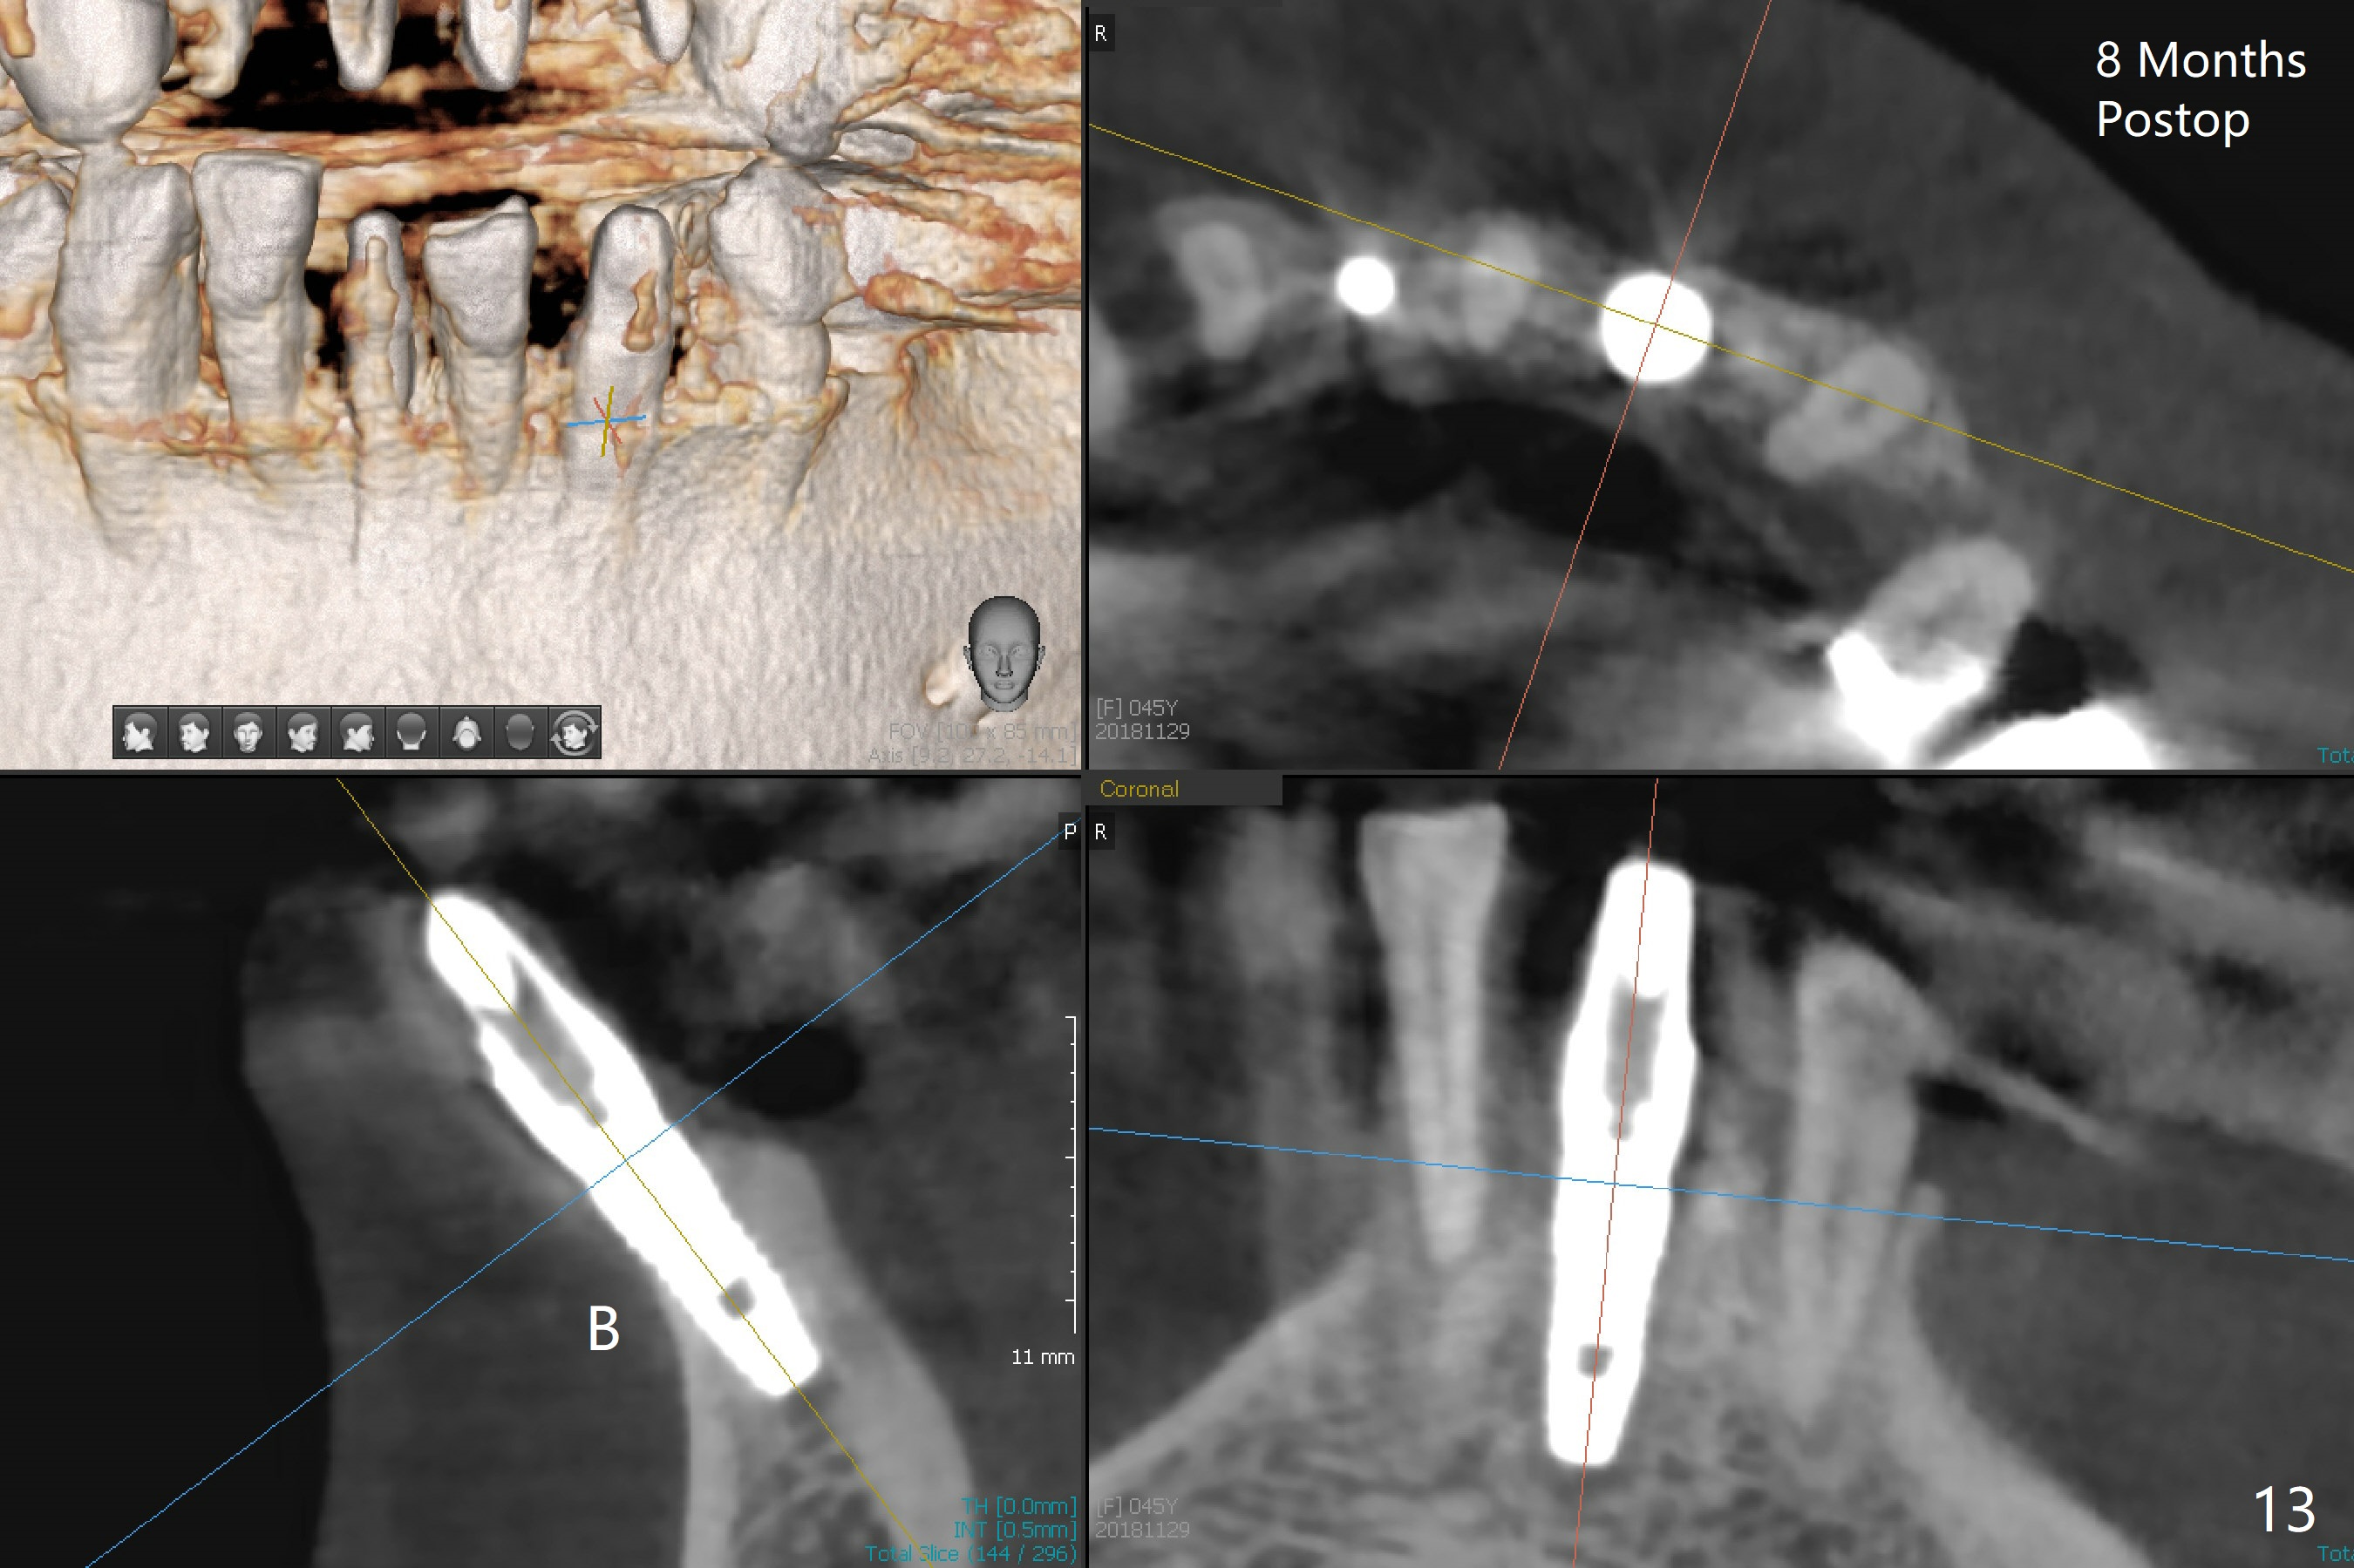

There is a fistula buccal to the apex of the tooth #23 preoperatively (Fig.1), which is related to loss of the buccal plate of the socket of #23. Therefore an implant is placed mainly in the socket of #22 (Fig.3). The lingual (Fig.2 L) gingiva appears to have more extensive inflammation. After extraction, the lingual (Fig.3 L) gingival margin is significantly lower than the buccal one. The lingual crest is ~ 4 mm lower than the buccal one. A 3.8x10 mm dummy implant is placed tentatively with an apical space (Fig.4). When a same dimension definitive implant is placed with 40 Ncm, it is 2 mm below the lingual gingival margin, whereas 6-7 mm below the buccal one (Fig.5). Vanilla graft is placed before placement of a 5.5x4(5) mm abutment (Fig.6,7). There is a 2-3 mm lingual (L) gap to be filled with the allograft secondarily to prevent periimplantitis (Fig.7). Later the abutment is changed to a longer and smaller one (Fig.8) with more of the allograft (*). After trimming of the abutment (Fig.9 (*: papilla between the fused teeth)), an immediate provisional is fabricated to close the socket (Fig.10, similar to Fig.1). The majority of the bone graft seems to be in place 8 months postop (Fig.12). The implant appears to have been placed buccal, consistent with the thin and slightly erythematous buccal gingiva (Fig.13). The ridge completely regenerates 2 years post cementation (Fig.14).